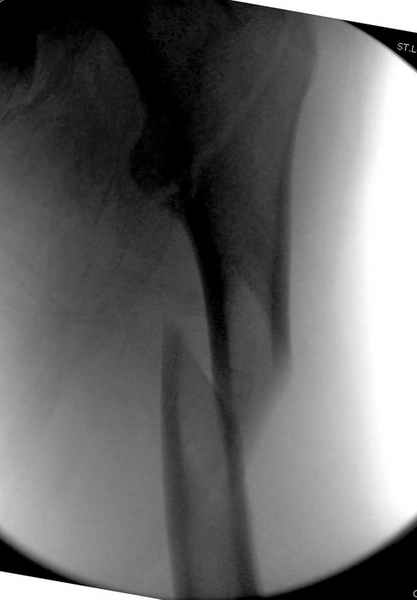

Дорогие коллеги,Как правильно определить такой перелом по классификации AO?

Как два отдельных или есть один соответствующий код? Фиксировать-то оба можно одним фиксатором...

Как раз недавно у меня был примерный случай: больному 36 лет, поступил ночью, травма в результате мотоциклетной аварии, кроме чрезвертельного и спирального перелома левого бедра имеется переломы костей предплечья с этой же стороны. Скелетное вытяжение, а на следующий день больной про оперирован на ортопедическом столе с дистракцией. Чтобы не расколоть чрезвертельный перелом провели временную спицу ближе к переднему кортексу, из малого разреза костодержатель для репозиции, а фиксацию провели антиградным штифтом. Этапы операции на снимках.

Да, сейчас это и у нас самый напрашивающийся выбор. Сделали гвоздем ChM, картинки в приложении.